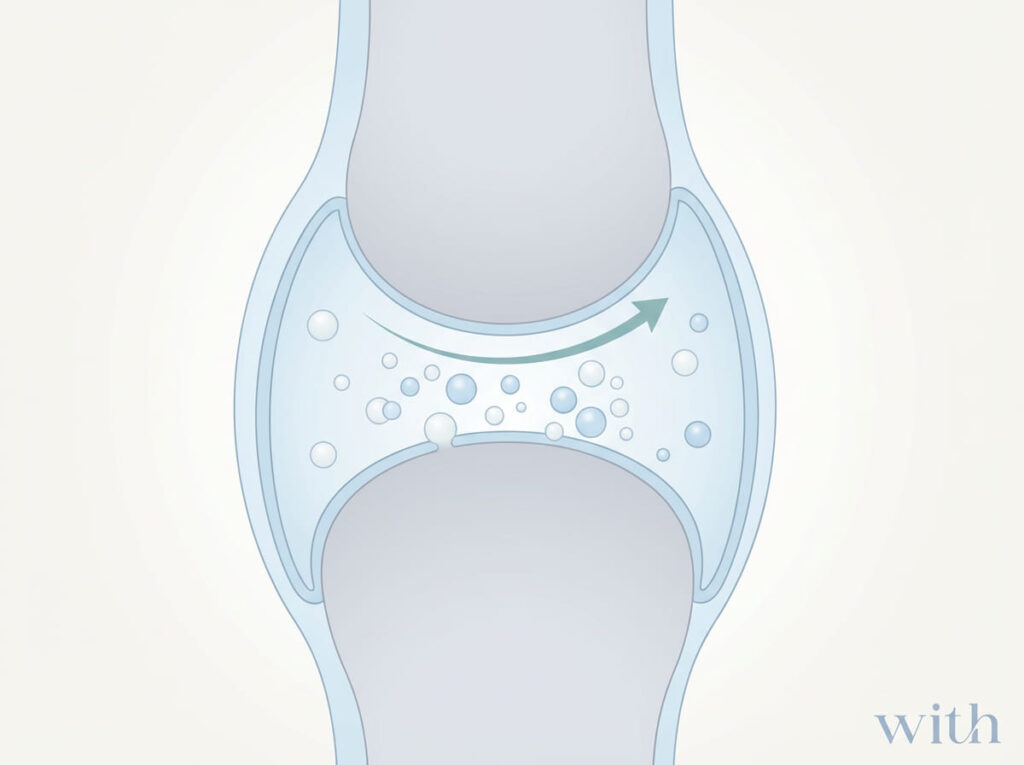

首が鳴るのはなぜ?(まず結論)

多くの「ポキッ」という音は、

関節内キャビテーションと考えられています。

リアルタイムMRI研究では、関節が鳴る瞬間に関節内に気泡が形成される様子が観察されました【論文①】。

これは、

- 骨がズレた音

- 骨同士が擦れた音

とは限らない、ということを意味します。

① 関節内キャビテーション(ポキッ)

急な関節牽引による圧変化【論文①】。